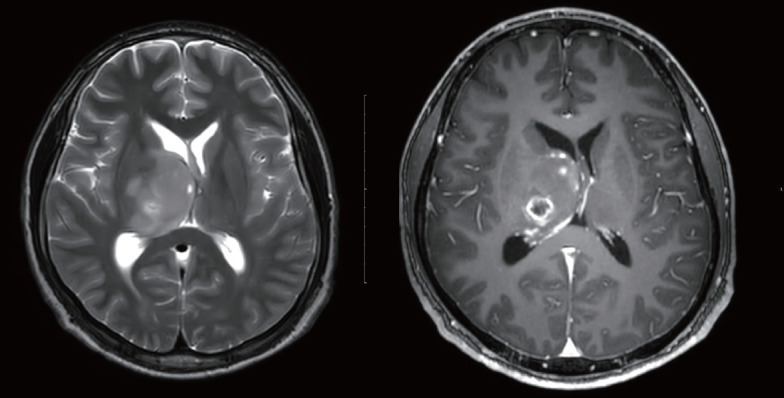

1型神经纤维瘤病(NF1)是一种普遍的遗传性疾病,其特点是广泛的临床表现,包括皮肤、神经和肿瘤并发症。该疾病由编码神经纤维蛋白的NF1基因突变引起,神经纤维蛋白是一种调节RAS/丝裂原活化蛋白激酶(MAPK)途径的肿瘤抑制因子。神经纤维蛋白功能的丧失使个体易患良性和恶性肿瘤,包括恶性周围神经鞘肿瘤、视神经胶质瘤和胃肠道间质瘤。此外,患有NF1的妇女在年轻时患乳腺癌的风险显著增加,需要加强监测措施。除了肿瘤风险外,NF1还经常与认知和行为障碍相关,包括学习障碍、注意缺陷多动障碍和社会沟通困难,这些都会对学业、职业和社会结果产生重大影响。此外,骨骼畸形、心血管异常和慢性疼痛等全身性并发症进一步加重了疾病负担。考虑到NF1的进行性和终身性,综合护理策略,包括多学科管理、早期发现和有针对性的干预措施,对于优化患者的预后至关重要。这篇综述强调了一种综合的终身管理方法的重要性,该方法可以解决NF1的医学和社会心理方面的问题。通过实施量身定制的监测计划和基于证据的干预措施,医疗保健提供者可以提高生活质量,降低与这种复杂疾病相关的发病率和死亡率。

Neurofibromatosis type 1 (NF1) is a prevalent genetic disorder characterized by a wide spectrum of clinical manifestations, including cutaneous, neurological, and oncological complications. The disease results from mutations in the NF1 gene, which encodes neurofibromin, a tumor suppressor that regulates the RAS/mitogen-activated protein kinase (MAPK) pathway. The loss of neurofibromin function predisposes individuals to both benign and malignant neoplasms, including malignant peripheral nerve sheath tumors, optic pathway gliomas, and gastrointestinal stromal tumors. Additionally, women with NF1 are at a significantly increased risk of developing breast cancer at a younger age, necessitating enhanced surveillance measures. Beyond oncological risks, NF1 is frequently associated with cognitive and behavioral impairments, including learning disabilities, attention-deficit hyperactivity disorder, and social communication difficulties, which significantly impact academic, occupational, and social outcomes. Moreover, systemic complications such as skeletal deformities, cardiovascular abnormalities, and chronic pain further contribute to the disease burden. Given the progressive and lifelong nature of NF1, comprehensive care strategies incorporating multidisciplinary management, early detection, and targeted interventions are essential to optimizing patient outcomes. This review highlights the importance of an integrative, lifelong management approach that addresses both the medical and psychosocial aspects of NF1. By implementing tailored surveillance programs and evidence-based interventions, healthcare providers can improve quality of life and reduce morbidity and mortality associated with this complex disorder.